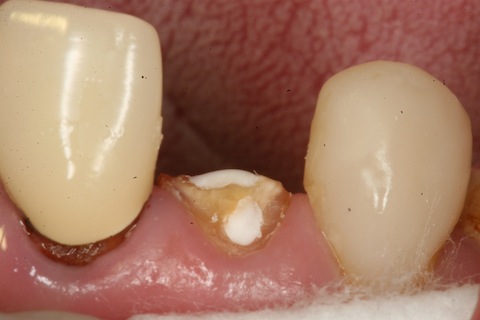

30代女性、右上2前装冠2次カリエスで根元から破折。

隣りの2番の前装冠が2次カリエスで折れました。

金属の方が歯よりイオン化傾向が大きいので歯の方が電気的に腐食します。

今日も残根にCRで歯を作りました。

αTCPセメントで覆髄して